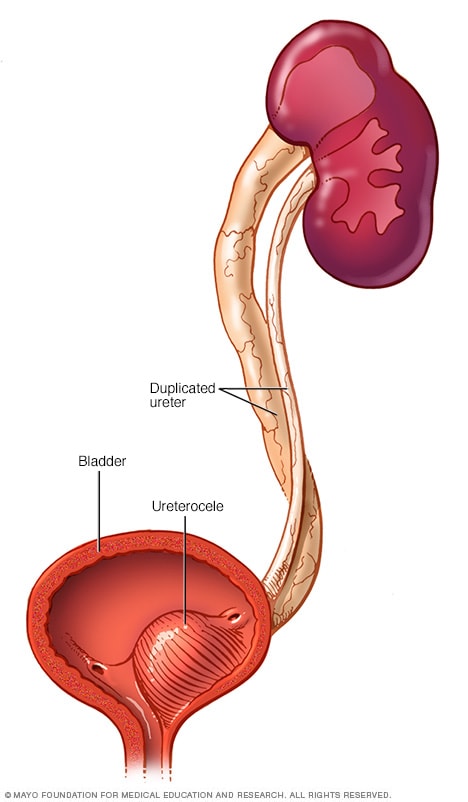

Рефлюксирующий мегауретер: Визуализация и медицинские изображения

Раздел: Фотопуть к знанию